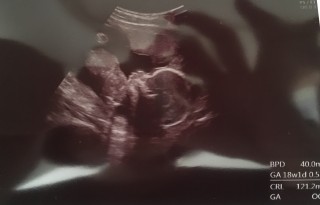

BPD40.8

FL 21.3

EFW177

ちゃんと指が5本見えます。

この姿がとても可愛いらしく、旦那と私の携帯の待ちうけにしちゃってます。

性別は未だ分かりませんでした。

前回より更に大きくなって子宮の中で窮屈そうに見えました(笑)